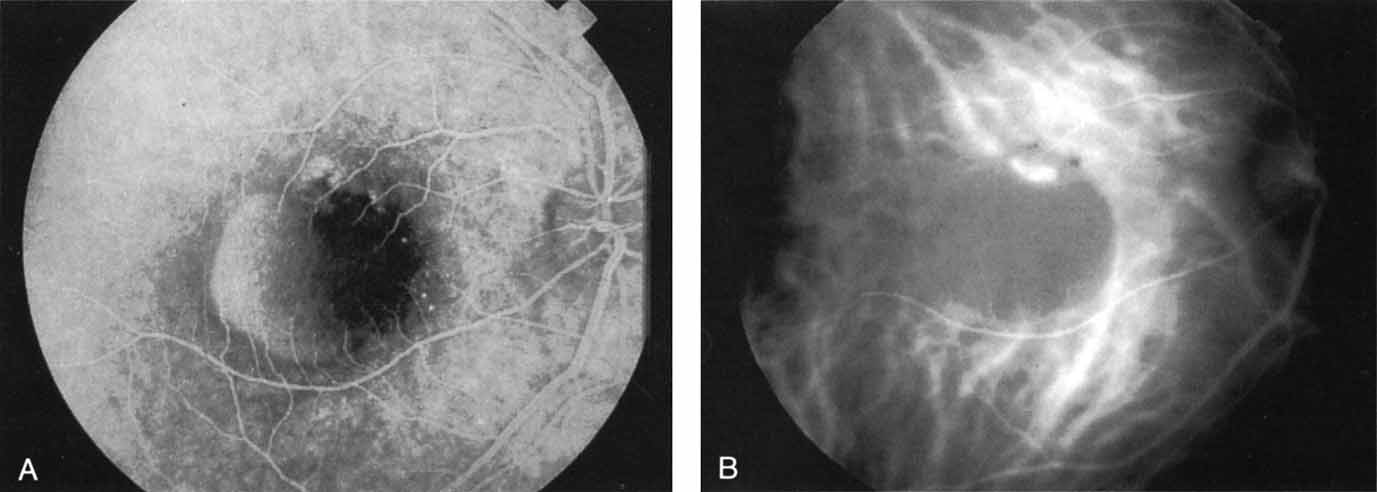

OCULAR HISTOPLASMOSIS SYNDROME

In contrast to multifocal choroiditis, ocular histoplasmosis syndrome does not demonstrate any large, hypofluorescent lesions on the ICG angiographic examination.69 Instead, there are frequently mid- and late-phase hyperfluorescent lesions in the posterior pole in areas that appear normal both clinically and on fluorescein angiography (Fig. 19). These hyperfluorescent lesions may represent sites of subclinical choroidal inflammation. The presence of these lesions on ICG angiography not only may serve to distinguish the histoplasmosis syndrome but also may serve to explain the apparent de novo appearance of new atrophic spots and CNV in what was previously presumed to be normal chorioretinal tissue.

Fig. 19 A. Clinical photograph of a patient with recurrent choroidal neovascularization associated with ocular histoplasmosis syndrome. A few focal “histo spots” are noted in the superior macula. B. Late-phase indocyanine green study demonstrating hyperfluorescence in the central macula corresponding to recurrent neovascularization. Multiple intensely hyperfluorescent dots are noted throughout the macular region, which do not correspond to any detectable lesion noted clinically or via fluorescein angiography. These focal spots may represent sites of subclinical inflammation at the level of the choroid.